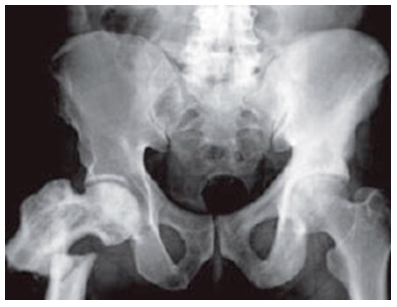

Quan som bebés, quasi tot l’os és cartílag. A mesura que anem creixent, el cartílag de l’esquelet es reforça amb sals minerals i es converteix en os. Aquest procés es diu ossificació i acaba cap als 18 anys en els homes i aproximadament als 16 en les dones.